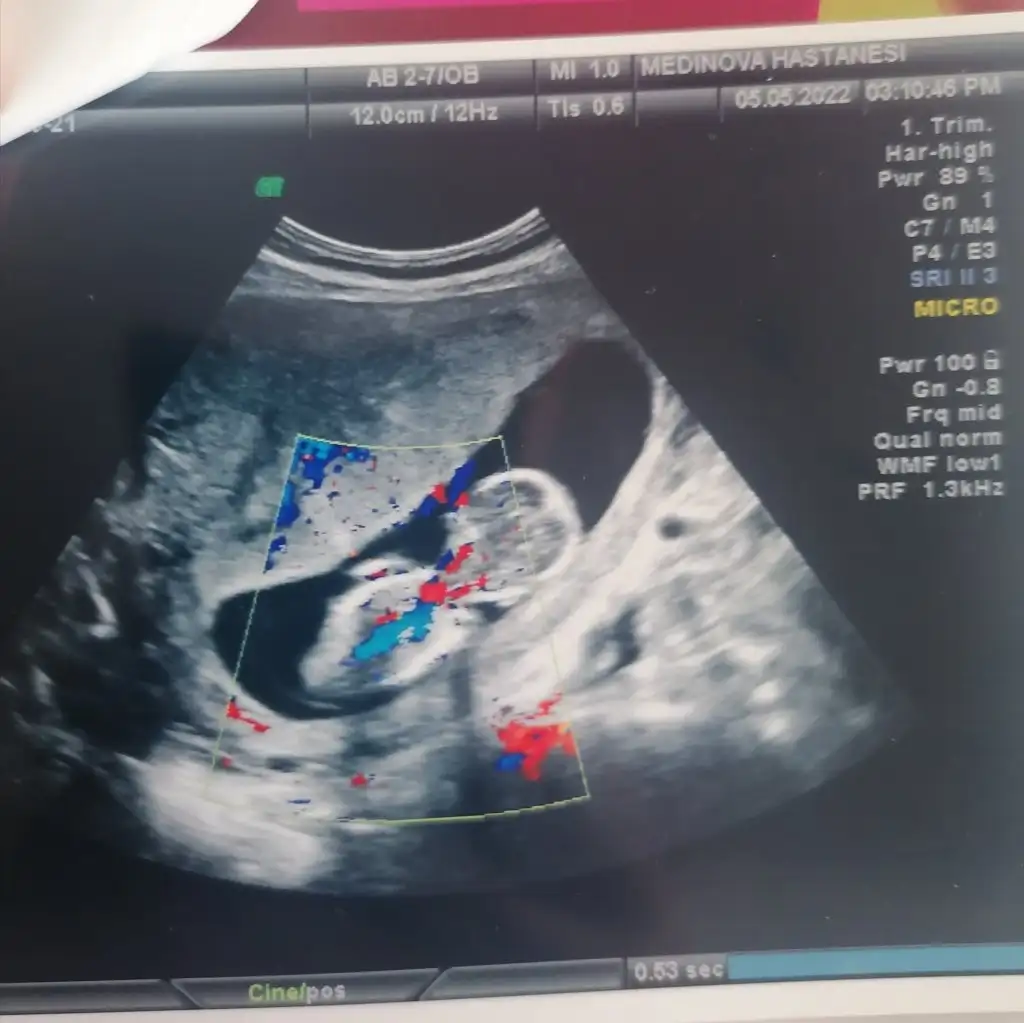

Bi çıkıntısını göremedim kız gibiBanada tahmin yaparmisiniz kizlar 12+1 bu arada plesanta tam karnimdaymis

Ayy hadi inşallah canım sağlıcakla dediğin gibi olsun doktorda çok baktı göremedi birşey söylemek için 1ay sonraya kaldı artık kesinlikBi çıkıntısını göremedim kız gibibacakları dik olduğundan da olabilir ama